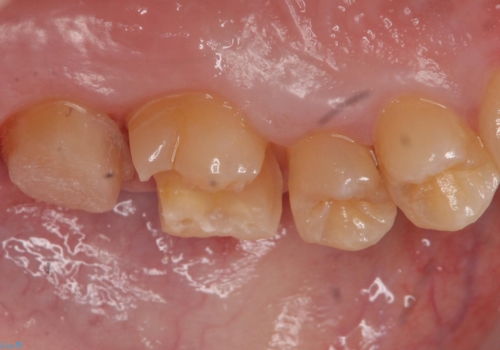

歯の表面に穴が開くほどの虫歯は歯の中でかなり大きくなっていることが多いです。

虫歯の除去後は適合の良い修復物を入れることで今後の虫歯リスクを減らします。